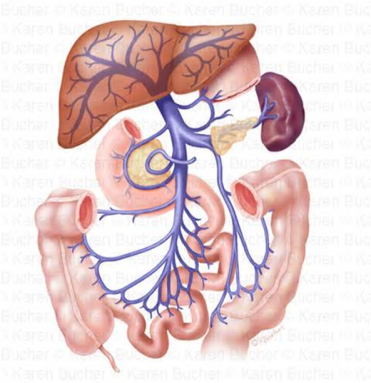

Digər kanserlər kimi kolon kanseri də proqressiv xəstəlik sayılır. Selikli qişadan başlayan proses 3 yolla yayıla bilir: yerli olaraq divar boyunca, qatlarına və ətraf orqanlara, limfatik yolla və hematogen (portal qanla qaraciyərə və digər orqanlara).

yob img 26